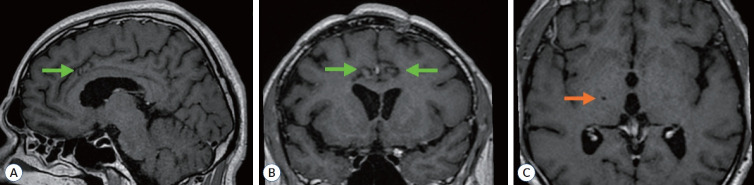

Stereotactic bilateral anterior cingulotomy, including lesions in the anterior and midcingulate cortex, is one of the methods used for treating thalamic pain syndrome. In cases of non-ischemic thalamic lesions, simultaneous stereotactic biopsy of the lesion can be performed in combination with cingulotomy. In this paper we present a case of a 45-year-old male with a lesion in the right thalamus, causing a severe contralateral hemi-pain syndrome. Bilateral radiofrequency anterior cingulotomy and stereotactic biopsy were performed during a single surgery. Pain completely subsided within a few days following the anterior cingulotomy. Histological examination identified a diffuse astrocytoma (World Health Organization grade II, ICD-O 9400/3), and the patient was subsequently referred for LINAC-based radiosurgery. The pain syndrome was controlled for 4 years, after which the pain syndrome returned with an increase in tumor size. Simultaneous anterior cingulotomy and stereotactic biopsy of the thalamic lesion represent a safe intervention for thalamic pain syndrome, enabling the alleviation of pain, verification of the lesion's etiology, and the application of appropriate treatment.

Abstract Image